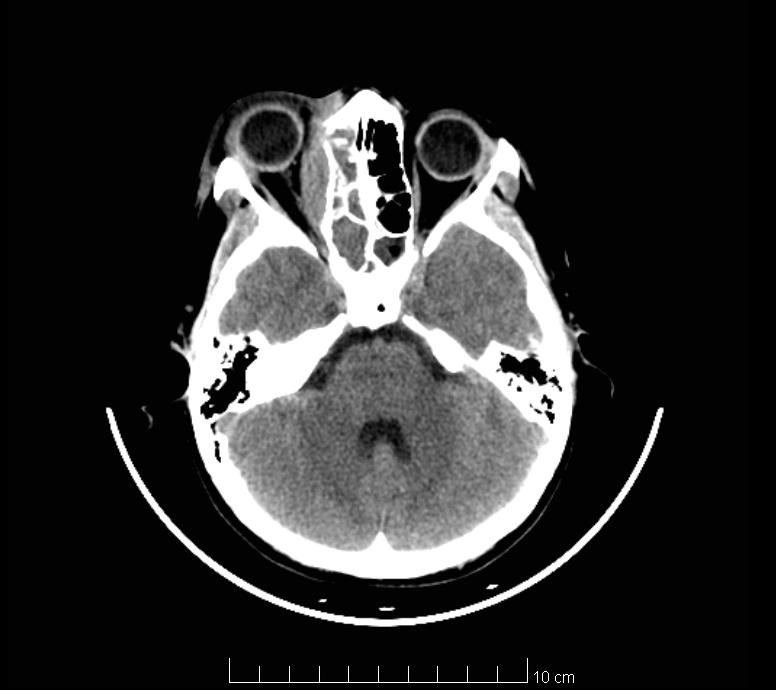

Imaging tests (brain CT and brain MRI) highlight right frontal lobe abscess (Fig. 2 – yellow arrow), medial orbital wall osteitis – right orbit (Fig. 1 – blue arrow, Fig. 2 – blue arrow), maxillary sinusitis, right ethmoidal and sphenoidal sinusitis (Fig. 1 – red arrow, Fig. 2 – red arrow).